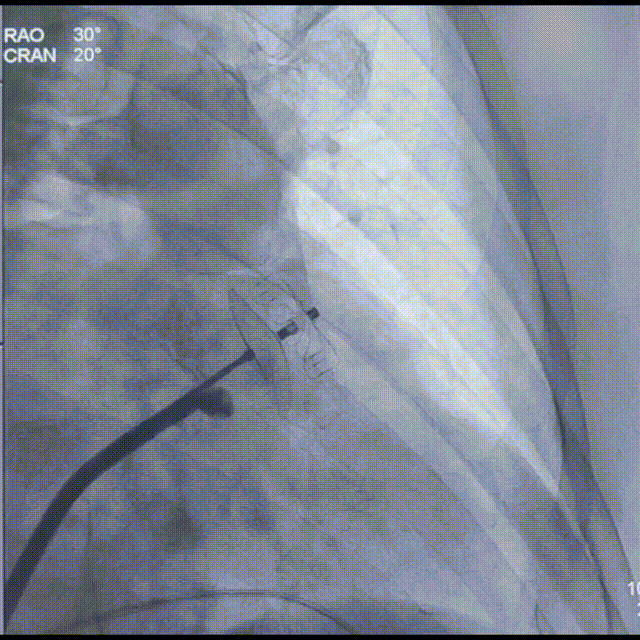

Laager®封堵器2631型号固定盘展开后造影

换用Laager®封堵器2631型号后造影提示位置良好,多体位下造影见封堵良好,封堵盘上缘在心耳口内,无残余分流;

封堵盘展开后,工作体位造影

封堵盘展开后,头位造影